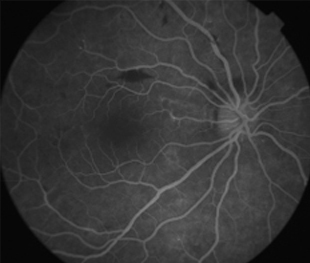

Angiografía OI

- Angiografía: teñido arterial, escape capilar, más tardíamente, no perfusion arteriolar y venular con teñido de las paredes vasculares y dilatación venosa.